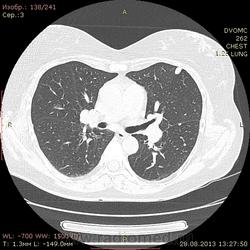

1961 г.р. В течение около 2х недель мучает сильный кашель, температура не поднималась, терапевны назначали антибиотики. Пропила неделю - без какого либо улучшения. Около полутора недель назад делали флюшку - без инфильтративных, корни немного расширены, структурны. Снгодня на флюшке появилась округлая тень слева. Решили сделать КТ - и вот результат.

Множественные мягкотканные мелкие узелки, лимфоаденопатия. Туберкалез? Саркоидоз? Mts? Не знаю чего и думать...прошу помощи.

1. Внутригрудная лимфоаденопатия. 2.Участки снижения пневматизации легочной ткани по типу "матового стекла". 3. Наличие в обоих легких узелковых образований (гранулем), преимущественно прилежащих к костальной, междолевой и межсегментарной плевре. Комплекс симптомов, наиболее характерен для Саркоидоза легких и ВГЛУ. Показано гистологическое подтверждение: трансбронхиальная внутрилегочная биопсия (информативность до 80% или медиастиноскоия и медистинотомия (информативность до 95%).

Лимфапролиферативное заболевание (ЛГМ, лимфома) vs саркоидоз. Нет тут туберкулеза.

На туберкулез легких не похоже.Лимфаденопатия. Метастазы. В меньшей степени вероятен саркоидоз.